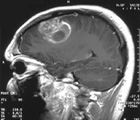

Response to therapy and disease progression will be evaluated with an MRI before each treatment cycle. Additionally, a beginning phase of the study will involve dosage increases until a maximum tolerated dose is established. Once the modernized dosing regimen has been established, additional patients will be subject to an optimal dosage regimen.

Glioblastoma multiforme is the most common and most malignant form of brain cancer. 17,000 brain tumors are diagnosed in the United States each year and approximately 60% are gliomas. Attention was drawn to this form of brain cancer when Senator Ted Kennedy was diagnosed with glioblastoma and ultimately died from it.